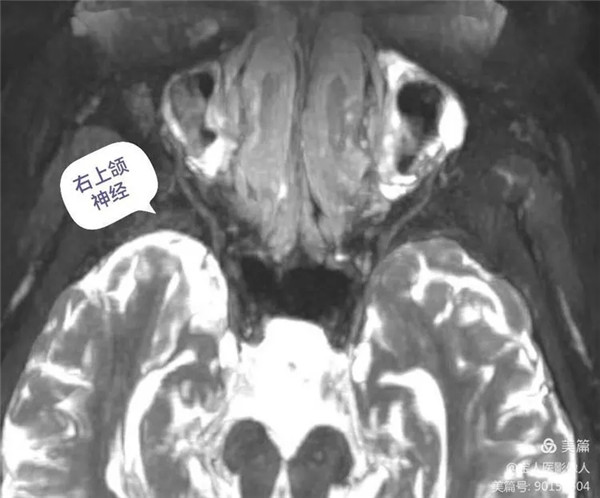

三叉神經顱外段第二分支-上頜神經

上頜神經自三叉神經節發出后,立即進入海綿竇外側壁,之后經圓孔出顱,進入翼腭窩,再經眶下裂入眶,續為眶下神經。上頜神經分支分布于上頜各牙、牙齦、上頜竇、鼻腔和口腔的粘膜以及瞼裂間的面部皮膚以及部分硬腦膜。